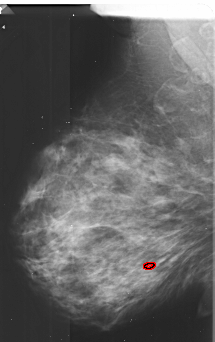

A_1031_1.LEFT_MLO

FILE: A_1031_1.LEFT_MLO.OVERLAY

TOTAL_ABNORMALITIES 1

ABNORMALITY 1

LESION_TYPE CALCIFICATION TYPE PLEOMORPHIC DISTRIBUTION LINEAR

ASSESSMENT 4

SUBTLETY 1

PATHOLOGY MALIGNANT

TOTAL_OUTLINES 1

BOUNDARY